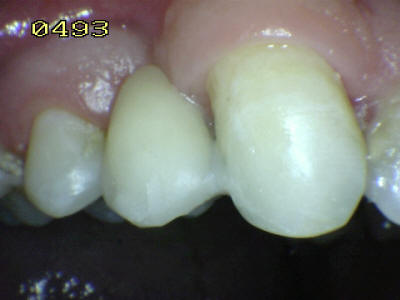

Paciente de sexo femenino de 35 años de edad, que presenta la falta de 23.

Se observa las líneas de extensión metálica del puente Maryland en las piezas talladas.